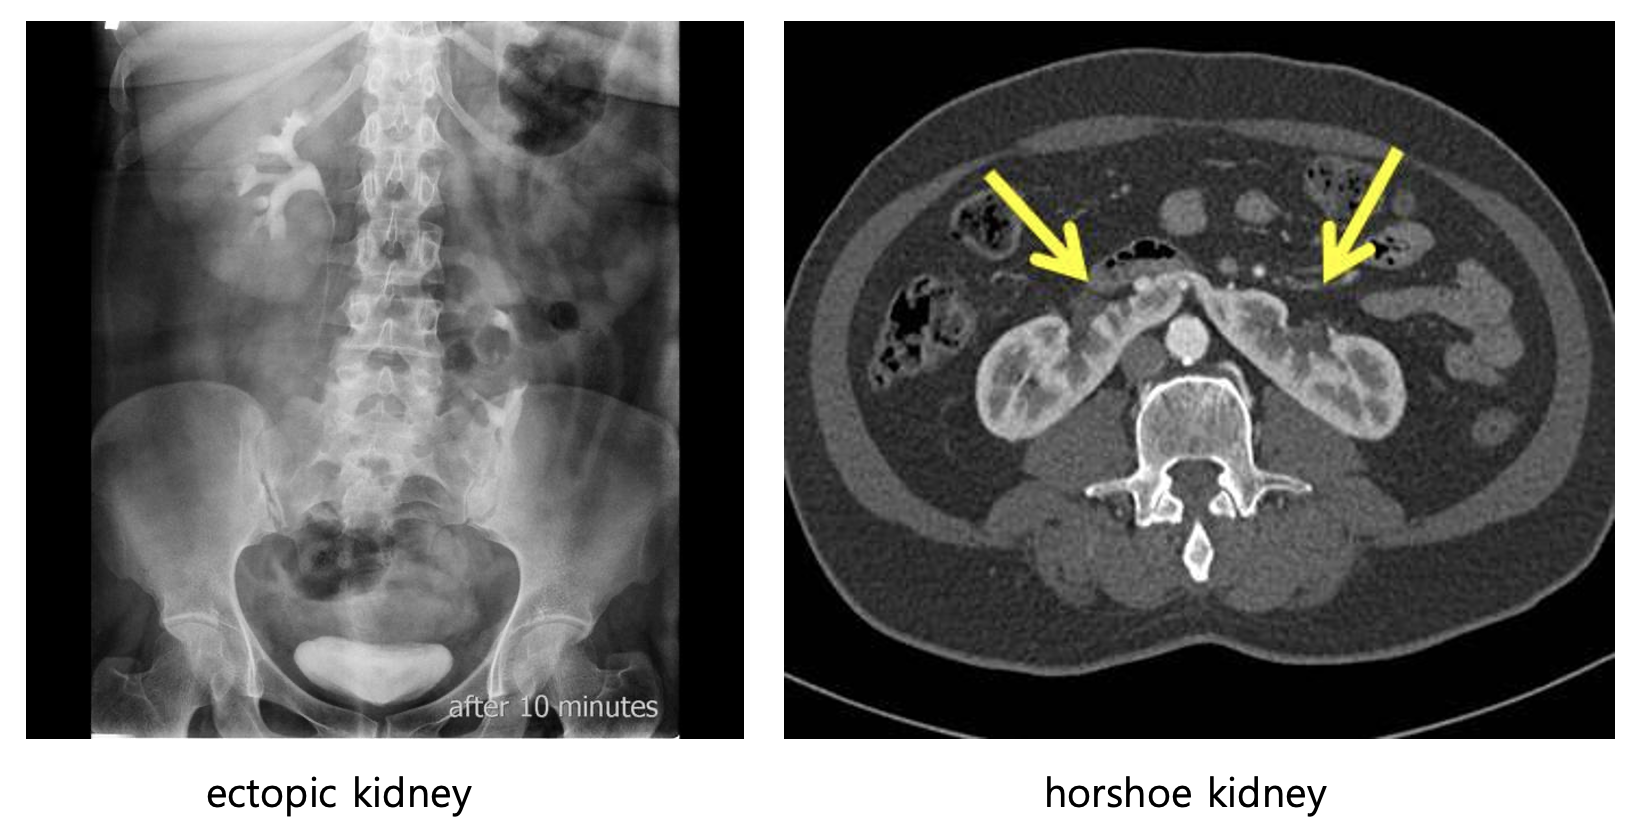

• 신장 딴곳증

• 신장 융합이상 (horseshoe kidney)